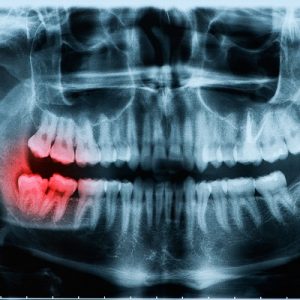

A process that uses radiations to take a picture of the whole mouth. The treatment is a popular one and is done before performing procedures like braces, extractions and dental implants to check the oral health of the patient. Although jaw is a curved part this X-Ray produce a simple straight image and it becomes easy for the doctor to diagnose the issue. X-Rays are the oldest way of producing the images but this particular method provides a wide analysis. The detector is placed inside the mouth and the ionizing radidations of the machine detect the problem.Â

With the treatment you can get the full image of the mouth. Infections, dental abnormalities and cysts are diagnosed by the procedure. Gum diseases are also identified. Many problems that can cause complications in the future will be diagnosed by the X-Ray. So the X-ray is versatlie and effective.Â